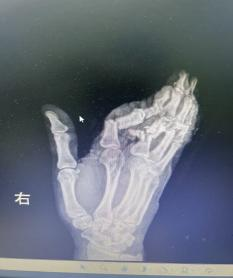

荊楚網(wǎng)(湖北日報網(wǎng))訊(通訊員 嚴玉嬌 戰(zhàn)慧瑩)2026年3月1日16時09分,一陣急促的鳴笛聲在街道上響起,一輛轎車跨越1個多小時的路程從云夢縣城飛馳而來,緊急停靠在湖北航天醫(yī)院急診科門前。車上,34歲的余女士(化名)面色蒼白,她的右手被厚厚的紗布包裹,殷紅的血跡已滲透多層敷料——她的右手食指、中指、無名指三指完全離斷,小拇指嚴重損傷,無力地垂在一旁。

1小時前,余女士還在工作,一個不留神,粉碎機擠壓到了她的手,右手瞬間卷入機器。劇烈的疼痛襲來,當她抽出手時,眼前的一幕讓她幾乎暈厥——食指、中指、無名指已完全離斷,只有少許皮膚還連著,小拇指也血肉模糊。

抵達醫(yī)院時,航醫(yī)骨外科值班醫(yī)生已接到通知,在急診待命。接到余女士的那一刻,值班醫(yī)生迅速上前為她查看傷情“您別擔心,一切有我們”,經(jīng)快速檢查,診斷明確:余女士的右手多指完全離斷傷。這是一類極為嚴重的手部創(chuàng)傷,斷指再植手術的黃金時間僅有6-8小時,一旦治療時間稍有延誤,難以保證手指存活。

手術的難度超乎想象:

血管細如發(fā)絲:手指的動靜脈直徑僅0.3-0.8毫米,醫(yī)生需要在顯微鏡下用比頭發(fā)絲還細的縫線進行吻合;

多指同時再植:余女士食指、中指、無名指三指離斷,需同時重建血運,給手術醫(yī)師的精力和體力帶來極大考驗;